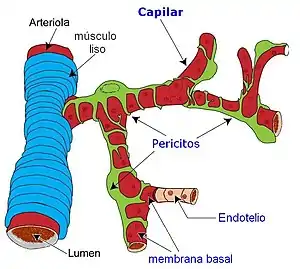

Estos vasos sanguíneos comprenden células endoteliales, células murales (pericitos y/o células de músculo liso vascular) y membrana basal.[1]

2.Capilar

- Un capilar sanguíneo es un vaso de diámetro entre 8 y 12 µm. Su pared está formada por una sola capa de células endoteliales y recibe pasivamente el flujo vascular que le llega.